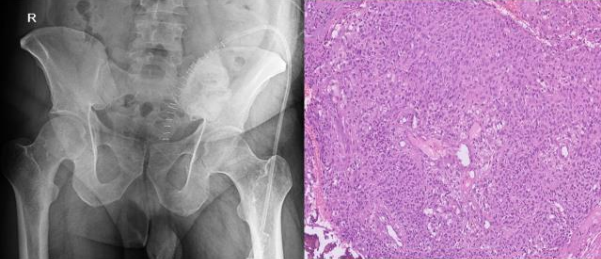

Case 3 - 35 year old male who presented with low back ache since 5 years and swelling since 2 year. Upon evaluation with X-ray of pelvis was found to have a lytic lesion in the left ileum on posterior aspect Fig-7. On MRI T2 hyper-intense lesion was found the posterior ileum with soft tissue component and cortical breech on posterior aspect measuring 5.7x 4.1x 7.3cm Fig-8.. Patient underwent extended curettage of the lesion and reconstruction with Poly-methyl methacrylate cement and Post-op Histopathology showed oval to spindle shaped cells with indistinct cell borders, round to oval hyperchromatic nucleus and moderate amount of cytoplasm- fibromatosis Fig-9. Upon follow up for 3 years patient is disease free.